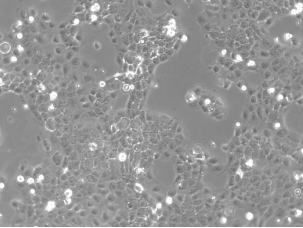

CaSki细胞是从小肠肠系膜转移灶的细胞中建立的。据报道,CaSki细胞含有完整的HPV-16(每个细胞大约600个拷贝)和HPV-18相关序列。

| 细胞形态 | 上皮细胞样 |

| 生长特性 | 贴壁细胞 |